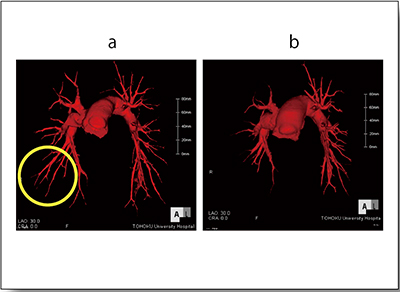

末梢型CTEPHでは複数回にわたって治療するため,3Dワークステーション上で治療日と治療した血管を記録することが非常に有効である(図5a)。症例4は前回左A9,今回は左A8の狭窄と末梢側の閉塞をターゲットに治療を行った。ターゲット領域をバルーンで拡張し,血流の改善が得られた様子が血管造影で確認できる(図5b,c)。また,Lung PBVでも左のS8,S9領域の血流改善が確認できる(図6a,b)。一方,肺野条件のmosaic perfusionでは評価が難しく(図6c),治療効果判定にはLung PBVが有用と言える。

図5 症例4:術中ガイド

a:3Dワークステーションでの治療記録

b:拡張前血管造影

c:拡張後血管造影

症例によっては,血管拡張術の治療前後の3D-CTAを比較すると,一見して治療した末梢領域の灌流が改善していることがわかる(図7)。しかし,症例5では,治療前CTAではスリット状の狭窄病変を認識しにくく,治療前後を比較しても効果判定は容易ではない(図8上段)。それに対してLung PBVは,治療前後の変化を把握しやすく,治療効果判定に適していると言える(図8下段)。

図7 症例4:血管拡張術前後の3D-CTA

a:拡張後

b:拡張前